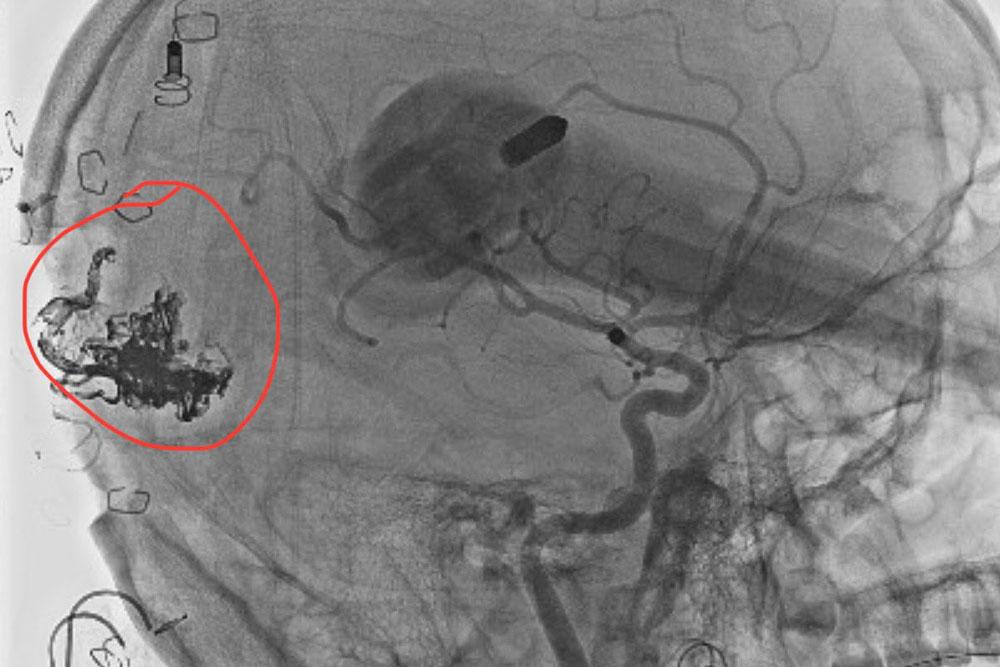

The advanced imaging revealed Logan had an arteriovenous malformation, or AVM, a tangle of blood vessels in the occipital–parietal area of the brain. Realizing neurosurgery may be needed, Logan and his family sought out the No. 1 ranked experts in the nation: NYU Langone’s Department of Neurosurgery.

Logan and his parents ultimately decided on having the AVM surgically removed by Dr. Riina and his team using an image-guided craniotomy technique for precision. The surgery, performed on July 17, 2024, went smoothly and Logan was discharged back home after three days of observation in NYU Langone’s Kimmel Pavilion.